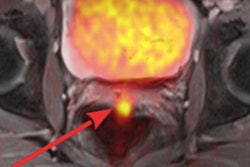

The prospective study from the Mallinckrodt Institute of Radiology at Washington University in St. Louis found similar results in a comparison of PET/MRI and PET/CT in terms of maximum standardized uptake values (SUVmax), metabolic tumor volume, and identifying disease location.

PET/MRI also offers the ability to compare tumor boundaries between PET and various MR sequences, said lead study author Dr. Maria Thomas, PhD, chief resident in radiation oncology. "The superior soft-tissue resolution is very valuable in assessment of pelvic malignancies, and we feel this will potentially replace PET/CT for radiation treatment planning at our institution in the future," she added.

With the addition of MRI to PET, the combined modalities have "the opportunity to visualize the integrated anatomic, metabolic, and functional imaging," she said. "Clearly, there is superior soft-tissue contrast for the pelvis and other disease sites, and the synchronous acquisition avoids differences in patient position, bladder and rectal filling, and tumor growth."